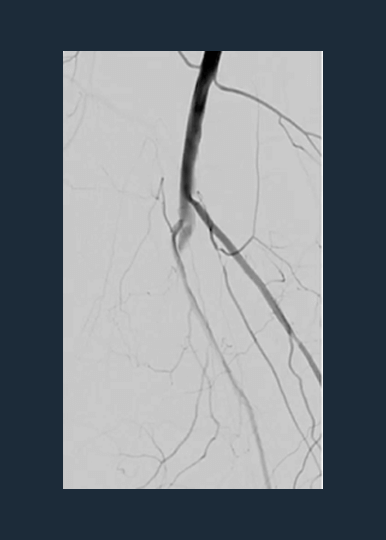

Shockwave M5+ is a versatile catheter, effective for above-the-knee (ATK) endovascular treatments.

The largest prospective real-world evidence for the treatment of complex, heavily calcified PAD